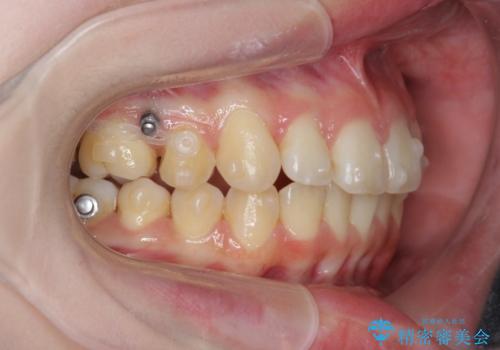

右側奥歯は上顎が相対的に前方に位置し(上顎前突)、そのため前歯の角度も突き出たようになり出っ歯のように見える状態でした。

マイクロインプラントを用いて、上顎奥歯を後方に移動させることで噛み合わせ・前歯の角度を改善していきます。

少し時間はかかりましたが、しっかりと綺麗な歯並びに仕上げることができ、大変喜んでいただくことができました。